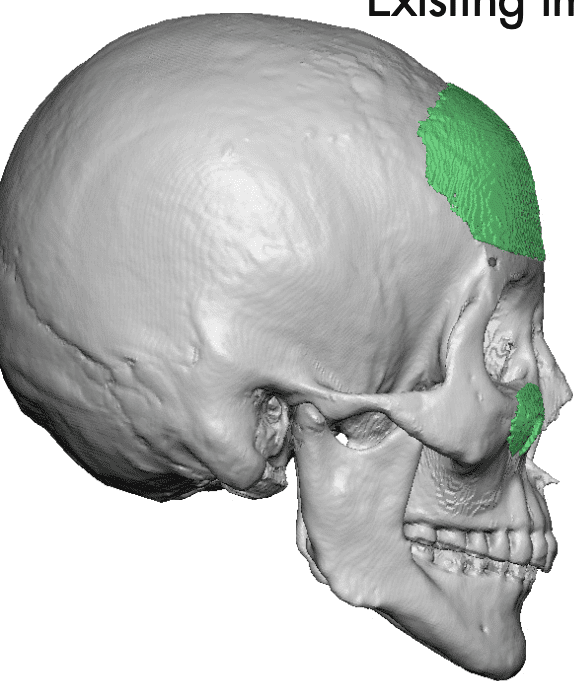

Occipital skull augmentation using a custom made implant designed from a measured template overlay on the depressed scalp area. Technically this was a 'scalp augmentation' using a bone-based implant.

Patient 23

Desire for correction of head shape which has a bilateral parasagittal skull shape deformity.

Skull augmentation using a custom skull implant inserted through an existing sagittal scalp incision.

Desire for correction of head shape which has a bilateral parasagittal skull shape deformity.

Skull augmentation using a custom skull implant inserted through an existing sagittal scalp incision.